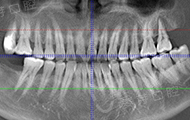

拍了片子,医生指出牙周膜增宽,左上根尖部阴影大,面部有稍微萎缩,为我制定了数字化精确种牙技术,其实也很好奇,现在种牙到底有多精确多快速,和医生约定好了时间,下次直接种牙。